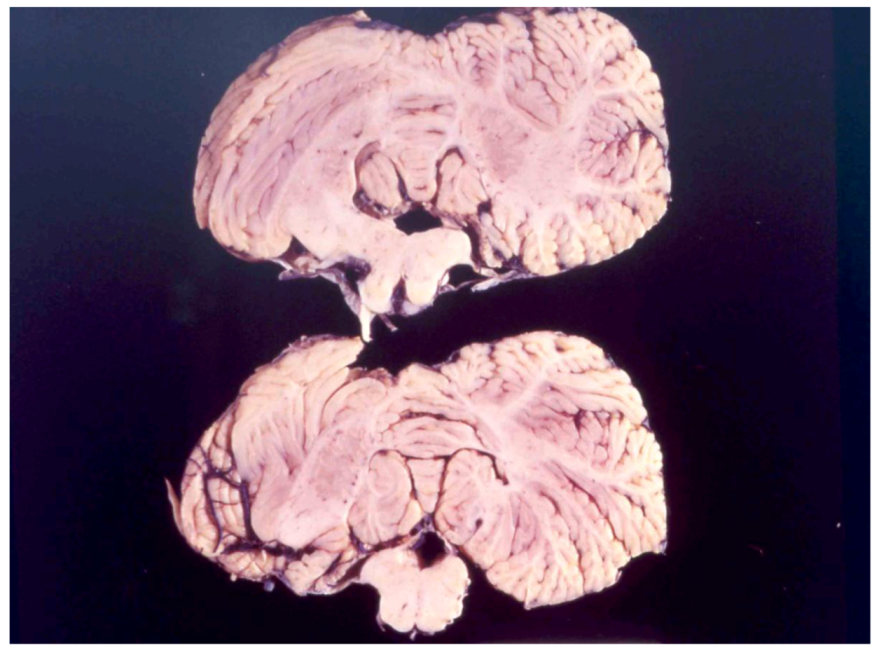

8. Neuropathology